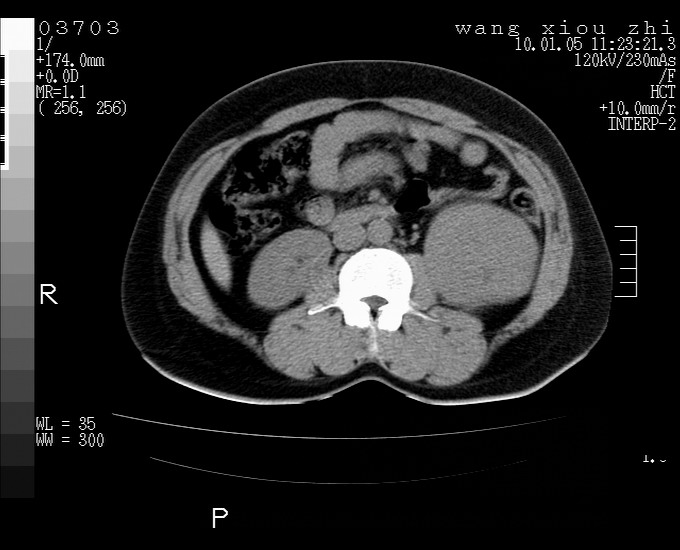

标题: CT23996:f,40.B超提示肿物。 [打印本页]

标题: CT23996:f,40.B超提示肿物。

左肾体积增大!下极见一密度略高团状软组织影!肾周结构组织未见明显异常!考虑左肾占位!建议增强!病史?

左肾占位,肾门及腹膜后淋巴结肿大,考虑透明细胞癌可能性大,建议增强

左肾体积增大,内见肿块影,考虑占位,建议增强。

左肾占位性病变,不排除肾癌可能;建议行进一步检查。

平扫等密度,增强来解决,重复肾也可能